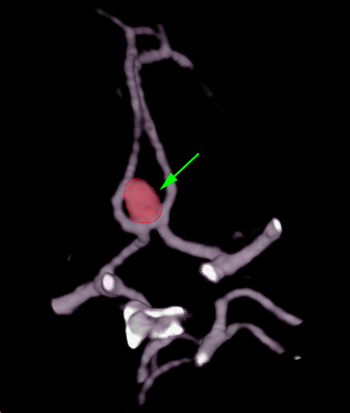

Ανεύρυσμα (περίγραμμα)